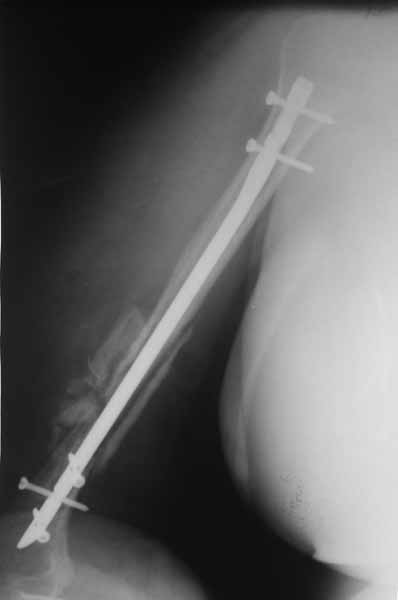

Re: Застарелый вывих головки плечевой кости

После БИОС